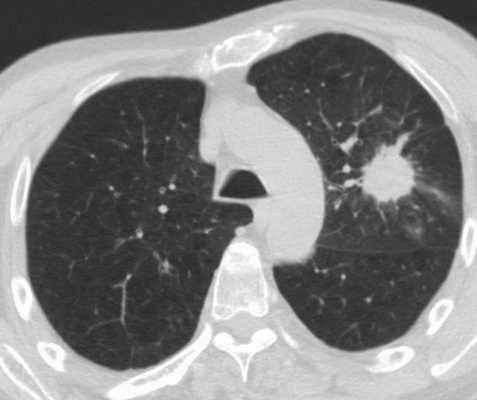

Фотографии и снимки КТ легких без контрастных веществ

Раздел: Визуальный дайджест